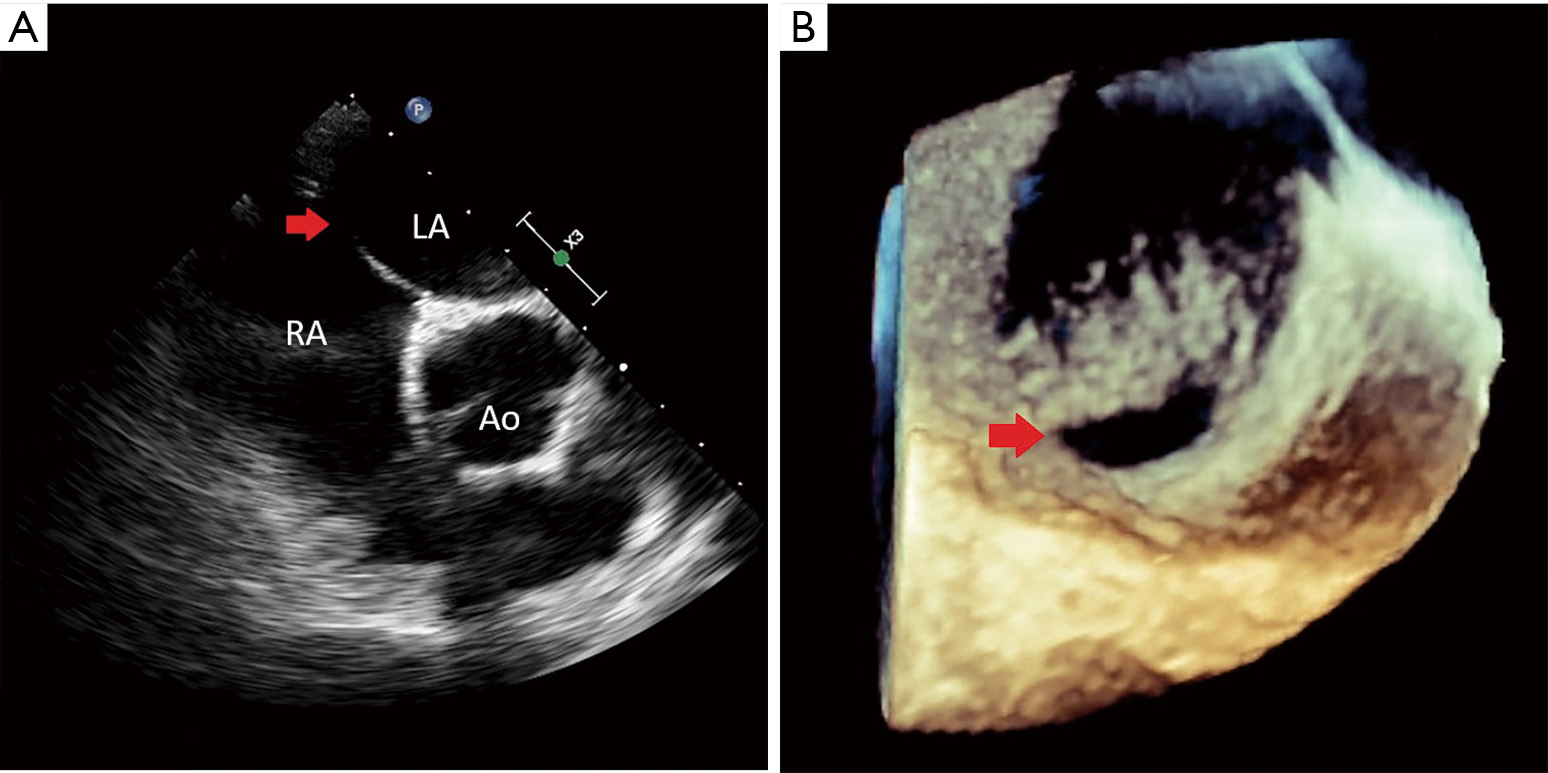

The role of real time 3Dtransesophageal echocardiography for safe and Journal Of Xiangya Medicine Published by ame publishing company. Gab1, a therapeutic target for allergic. We are excited to introduce our newest journal, journal of xiangya medicine (j xiangya med; The journal of xiangya medicine publishes invited articles solicited from recognized experts in their fields as well as free submission articles, in the. Find the latest published papers in journal of xiangya medicine +. Journal Of Xiangya Medicine.